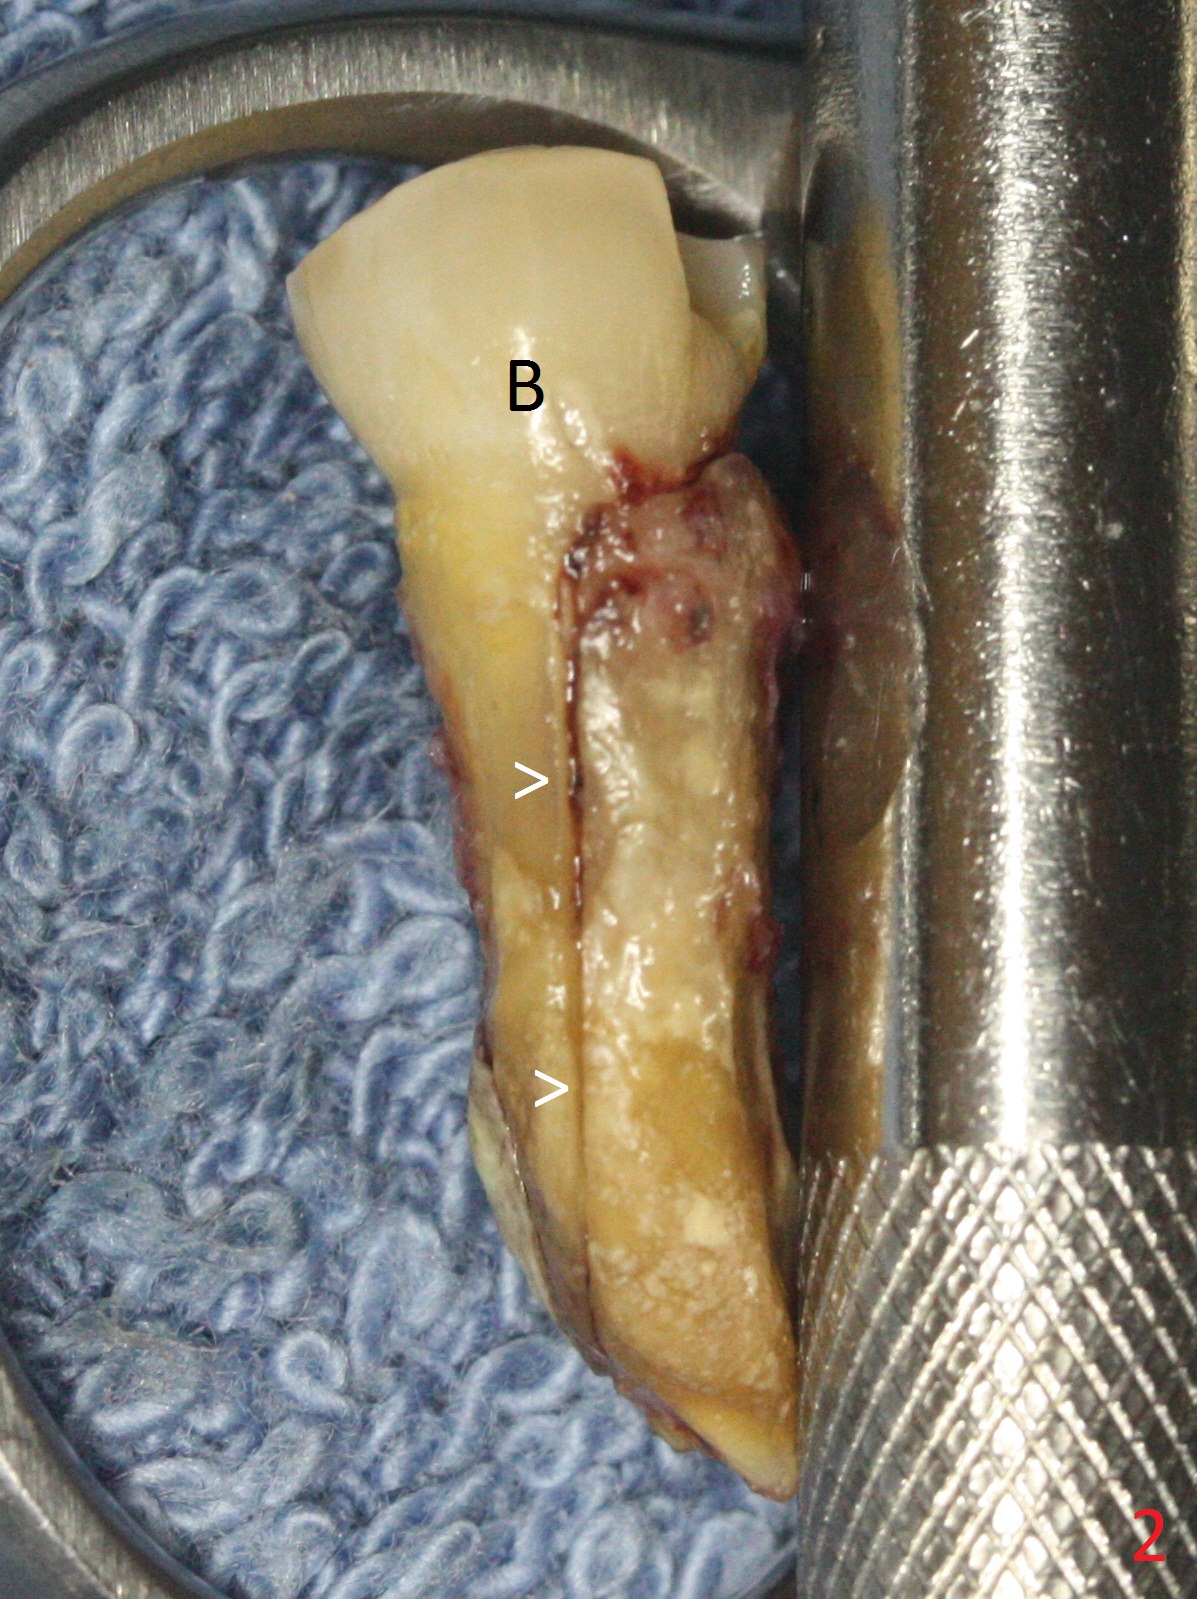

Extraction of the lower left 2nd premolar with vertical fracture (Fig.1,2 >) is easy because of peri-radicular radiolucency.  The apical end of the osteotomy is not shown with a 2 mm pilot drill (Fig.3) or a 3.8x18 mm implant (Fig.4) in place.  It appears that the implant is not placed deep enough.  Following 3-4 more turns of the implant and placement of a 5.5x4(3) mm abutment (Fig.5 A), allograft is placed (*).  A postop panoramic X-ray is taken (Fig.6); the osteotomy could have been deepened to reduce the possibility of periimplantitis.  Retrospectively, the panoramic X-ray should be taken after use of the pilot drill. The bone around the implant appears to have regenerated 4 months postop (Fig.7,8).  Bone density appears to continue increasing 9 months postop (i.e., 4.5 months post cementation, Fig.9).  Bone loss is minimal 2 years post cementation (Fig.10).